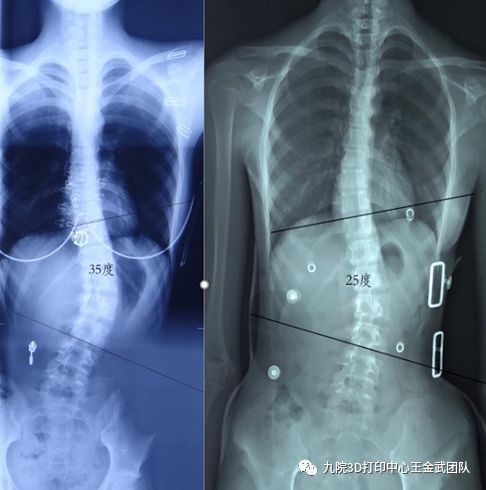

复查

2019年1月,自述穿戴期间每天能够佩戴22h以上,但由于学习紧张,运动与锻炼时间较少。从体表观察,经过5个月矫形器治疗后,患者身体仍然向左偏移,但已经有明显好转;剃刀背情况也得到明显改善,骨盆偏移得到改观。

结合患者近期的矫正,对其进行适当调整,增加垫片,建议2个月后行X光片检查。后期根据X光确认矫形器是否需要进行调整。